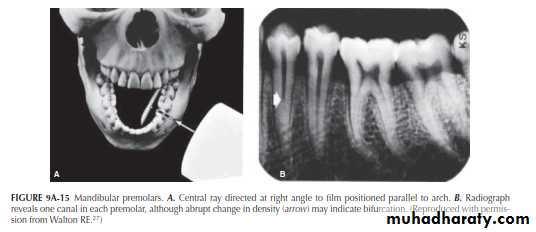

Mandibular Premolars

The importance of varying the horizontal angulation for mandibular premolars is demonstrated in Figure 9A-15A. The central beam is directed at a right angle to the film. What appears to be a single straight canal is discernible in each premolar (Figure 9A-15B).Mandibular Premolars

There is an indication, however, in the image of the first premolar that the canal might bifurcate at the point of the abrupt change (“fast break”) in density (arrow). Directing the central ray 20° from the mesial in the first premolar (Figure 9A-16A) causes the bifurcation to separate into two canals (Figure 9A-16B). The tapering outline of the tooth, seen in both projections, would indicate, on the other hand, that the two canals undoubtedly rejoin to form a common canal at the apex. In both the right-angle and 20° variance projections, the second premolar appears as a single canal.Maxillary Molars